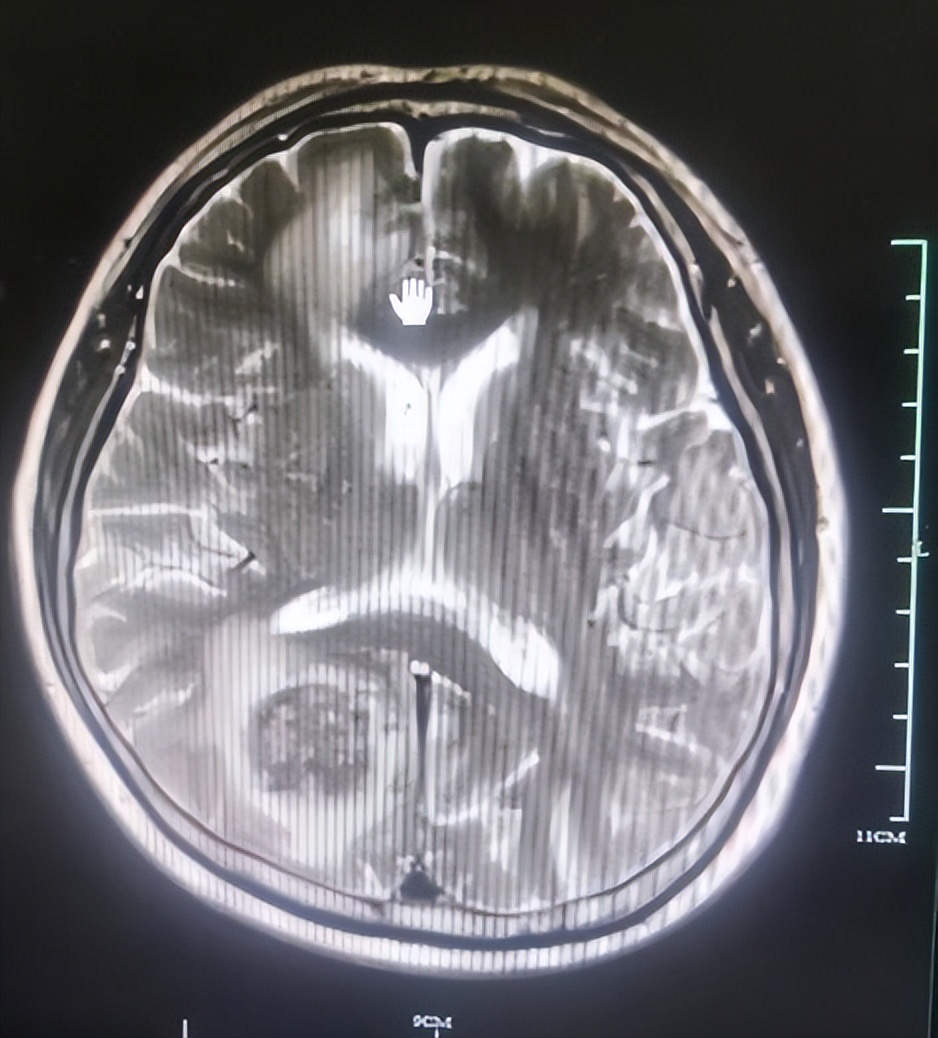

于是于2022年10月3日进行局部姑息性放疗5次,采用的是SBRT-IGRT放疗技术,靶区包括胸椎,之后于2022年10月20日进行了两周期信迪利单抗+呋噻替尼方案治疗,复查头颅MRI显示:双侧大脑半球多发结节较前缩小,周围脑水肿减轻。复查腰椎CT后,病灶较前稍缩小(如下图),疗效评估为疾病稳定(SD),于是为田女士办理了出院。

图为田女士复查头颅MRI情况

田女士刚入院时,左侧肢体活动受限,头晕头痛,确诊为直肠癌伴多发转移,经局部放疗、免疫联合靶向治疗后,田女士的病情有了明显控制,左肢可以正常活动,没有头晕头痛、恶心呕吐、腹胀腹痛等不适,复查CT后显示病灶较前缩小,疗效评估为疾病稳定(SD),于是为她办理了出院,叮嘱她三周后来院再次以原方案进行治疗。同时也提醒她出现头晕头痛时,尽量卧床休息,改变体位时动作宜缓慢,必要时监测血压。保持地面干燥,无障碍物,防止患者摔倒或滑倒。